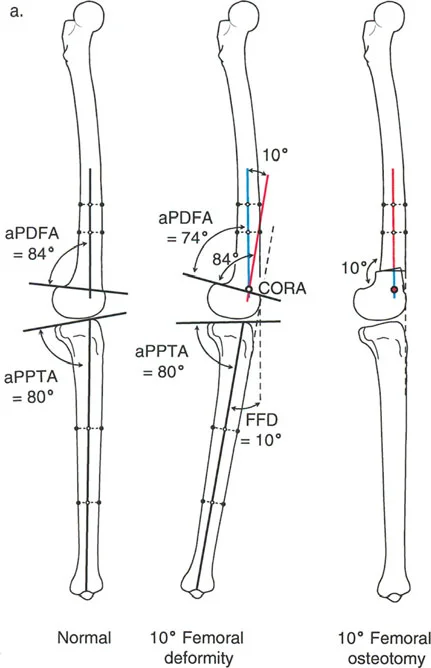

- الأشعة السينية الطويلة للطرف السفلي بالكامل أثناء الوقوف (Standing Long-Leg AP View): تُعد هذه الأشعة حاسمة لتقييم المحاذاة الميكانيكية للطرف السفلي بأكمله. تُظهر بدقة درجة الانحراف الأفحج (Varus) أو الأروح (Valgus) وتساعد في تحديد مركز دوران التشوه (CORA).

علاج خشونة المفصل أحادي الحجرة الإنسية (MCOA)

غالبًا ما ترتبط خشونة الركبة الإنسية بالانحراف الأفحج (Genu Varum). يهدف العلاج إلى تحويل الحمل من الحجرة الإنسية المتضررة إلى الحجرة الوحشية السليمة.

- قطع العظم الفخذي البعيد (Distal Femoral Osteotomy - DFO):

- قد يكون ضروريًا إذا كان التشوه الأفحج يتركز في عظم الفخذ.

علاج خشونة المفصل أحادي الحجرة الوحشية (LCOA)

ترتبط خشونة الركبة الوحشية غالبًا بالانحراف الأروح (Genu Valgum). يهدف العلاج إلى تحويل الحمل من الحجرة الوحشية المتضررة إلى الحجرة الإنسية السليمة.

- قطع العظم الفخذي البعيد (Distal Femoral Osteotomy - DFO):

- يُعد الخيار الأكثر شيوعًا، حيث يتم عمل قطع في الجزء السفلي من عظم الفخذ لتصحيح الانحراف الأروح.

- قطع العظم الظنبوبي العلوي (High Tibial Osteotomy - HTO):

- يمكن استخدامه إذا كان التشوه الأروح يتركز في عظم الساق.

- ملاحظة هامة: يجب تصحيح LCOA إلى محاذاة محايدة (MAD = 0 مم) فقط، على عكس MCOA التي غالبًا ما يتم تصحيحها بشكل مفرط قليلاً إلى وضعية الأروح. هذا لتجنب تحميل زائد على الحجرة الإنسية.